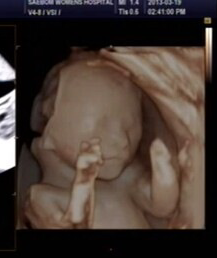

자작도아니고 합성도 아니고 미국아이초음파사진도 아니예요.

그날찍은 다른 초음파사진 더 올릴게요.

날짜랑시간까지다찍혀있어요...

이모가 태어날 조카 초음파사진이 너무신기하고 이뻐서 올린사진이예요ㅎ

동생이 지금 임신중인데...

이번에검진갔다 초음파사진을 찍었는데 혼자보기 아깝고 넘 신기해서요ㅋ

일케완벽하게쁘이를ㅎㅎ 신기하지않나요?? ㅎ

(왼쪽 뇌가 저렇게 나오는것은 뇌가 덜 생긴게 아니라 초음파를 찍을때 약간 선명하게 나오는정도를 오른쪽 부분으로 맞춰서 그런겁니다. 다시 왼쪽 부분 쪽으로 맞추면 왼쪽 부분이 완성되서 나오구요 저때 되면 손가락 발가락 뇌 뼈 두개골형태 하며 있을꺼 다 있습니다)